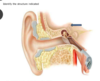

what is 10?

- Tibiotalar ligament

- tendon of tibialis anterior

- spring ligament

- Deltoid ligaments of the ankle

- calcaneal tendon

what is 10?

- Tibiotalar ligament

- tendon of tibialis anterior

3. spring ligament - Deltoid ligaments of the ankle

- calcaneal tendon